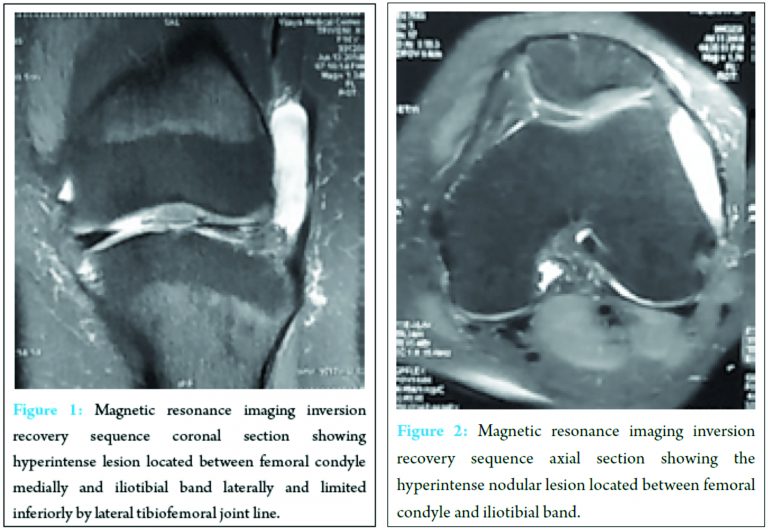

A 16-year-old female presented with a history of several months of left lateral knee pain. She also complained of a movable mass at the lateral joint area during ambulation. An MRI scan of left knee was performed. The MRI showed a thickened ITB and oval abnormal altered signal intensity lesion appearing heterogeneously hyperintense on inversion recovery sequences (Fig. 1,2), hypointense on T2-weighted images measuring about 4.1 cm × 2.7 cm × 0.8 cm (cephalocaudal X anteroposterior X mediolateral) located between femoral condyle medially and iliotibial band laterally and is limited inferiorly by lateral tibiofemoral joint line. A well-demarcated, ovoid nodular lesion was also observed in the compartment-like space. The initial diagnosis based on the MRI findings, clinical history, and physical examination was ITB friction syndrome. We suspected the nodular lesion was a ganglion, focal synovial thickening, focal villonodular synovitis, or focal degenerative change of invaginated extra-articular fatty tissue.